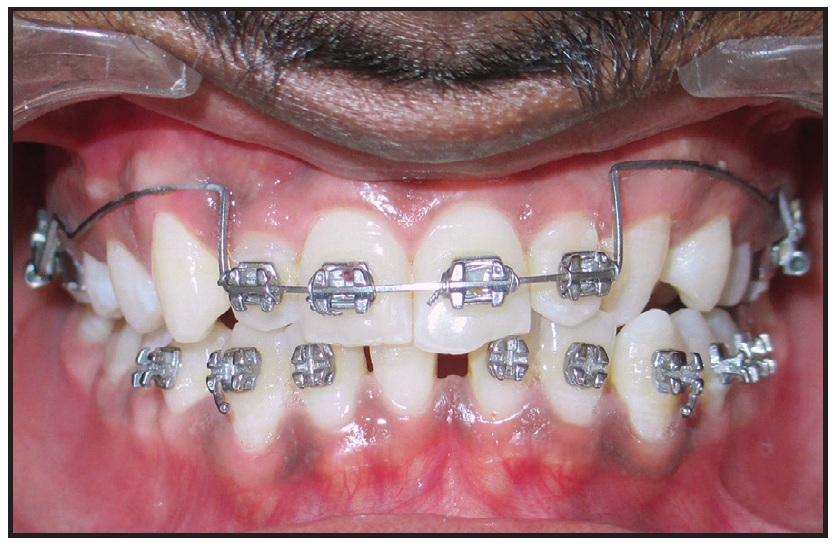

The posterior bite plate was trimmed occlusally at each monthly visit, and the patient was assessed for signs and symptoms of TMD. Positive overjet and overbite were achieved in nine months (Fig. 3). The upper canines and premolars were bonded, and reverse-curve .016" × .022" nickel titanium archwires were inserted for three months of leveling.

Fig. 3 Positive overjet and overbite achieved after nine months of treatment.